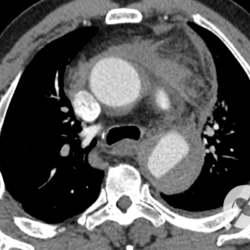

Outro caso de aneurisma dissecante da aorta, que compromete a aorta nos segmentos ascendente e descendente. Aqui podemos identificar com clareza qual a luz verdadeira e qual a falsa. O maior diâmetro é o da falsa luz, mas além deste fato observamos que a falsa luz tem menor quantidade de contraste, o que ocorre em virtude do seu fluxo ser mais lento, de menor pressão. Outro dado extremamente importante é a presença de um pequeno derrame pericárdico, secundário a uma dissecção do “flap” intimal para o pericárdio, que pode levar a um quadro de tamponamento cardíaco.